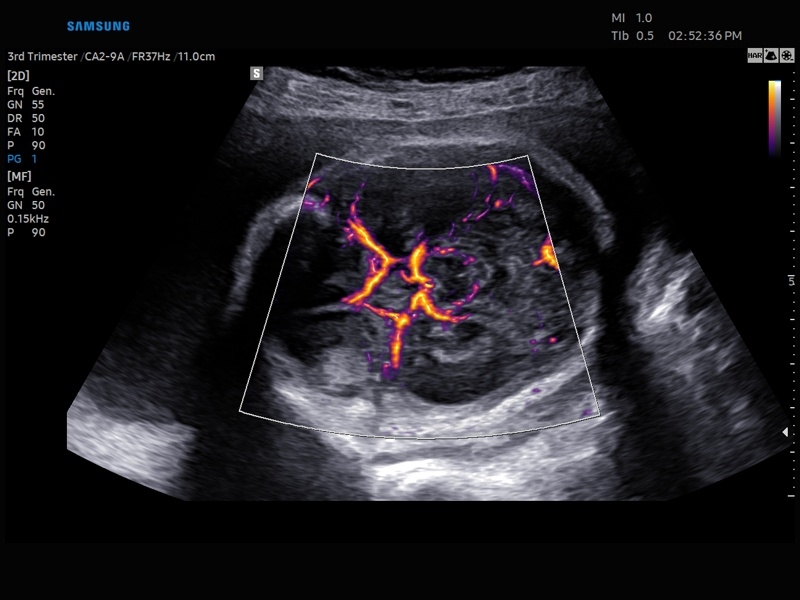

Ультразвуковой сканер V8-RUS является экспертным классом (премиальный уровень) и производится компанией Samsung Medison. Сканер V8 обеспечивает превосходное качество изображения благодаря использованию технологии Crystal Architecture™, которая включает в себя передовое аппаратное обеспечение, монокристальную технологию изготовления датчиков и сложную программную обработку ультразвуковых лучей.

• Технологии визуализации: MV Flow, LumiFlow, SEE Stream, Panoramic

• Модуль MV-Flow – программа (режим), позволяющая визуализировать кровоток в микроциркуляторном русле с высоким разрешением без использования контраста.

• Модуль LumiFlow – программа отображения кровотока с объемной графикой для лучшего понимания архитектоники сосудистого русла.

• Программа SEE Stream – режим недопплеровской визуализации кровотока в реальном масштабе времени.